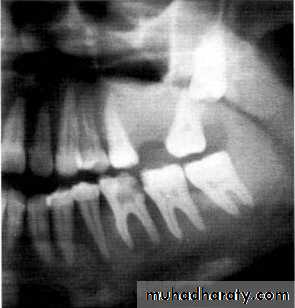

Traumatic cyst*Mandible > Maxilla. <20 years of age.

*Asymptomatic, expansile, associated with history of trauma. *Extend between the roots of teeth with scalloped border .

*Aspiration is not productive, empty cavity.